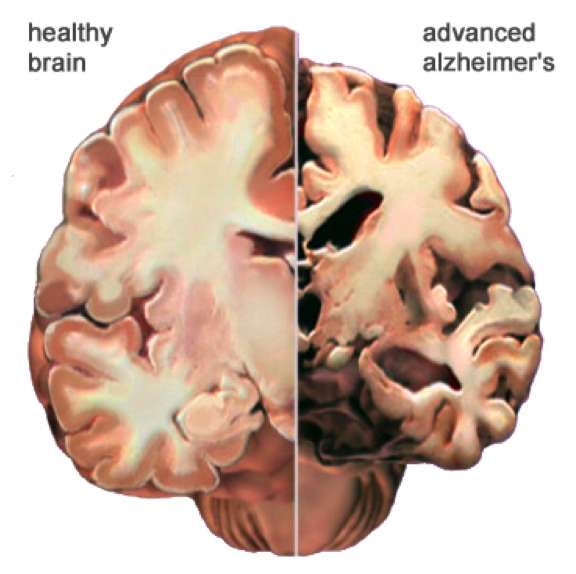

Alzheimer’s Dementia is the most common form of dementia, accounting for 60-80% of all dementia cases worldwide. While many people think of it simply as “memory loss,” Alzheimer’s Dementia is actually a complex brain disorder that affects thinking, behavior, and the ability to perform everyday activities. The disease develops when abnormal protein deposits, amyloid plaques, and tangles build up in the brain, disrupting communication between brain cells and eventually causing them to die. This process typically begins years before symptoms become noticeable, which is why early detection and understanding of Alzheimer’s Dementia is so crucial for families.

What makes Alzheimer’s Dementia particularly challenging is that it doesn’t just take away memories, it can change personality, affect judgment, and make familiar tasks feel impossible. The person you’ve known and loved is still there, but they’re experiencing the world through the filter of a changing brain.

The middle stage of Alzheimer’s Dementia often lasts the longest and requires the most significant adjustments for families. Memory loss becomes more pronounced, and your loved one might not recognize familiar faces or remember important life events. Simple tasks like getting dressed or preparing meals become challenging.

This is when families often see the biggest changes in personality and behavior. Someone who was always gentle might become agitated, or a person who loved socializing might withdraw completely. These changes aren’t choices—they’re symptoms of how Alzheimer’s Dementia affects different areas of the brain.

In the advanced stages of Alzheimer’s Dementia, verbal communication becomes limited, and your loved one will need help with all daily activities. This stage is often the most emotionally difficult for families, as the person they knew seems increasingly distant.